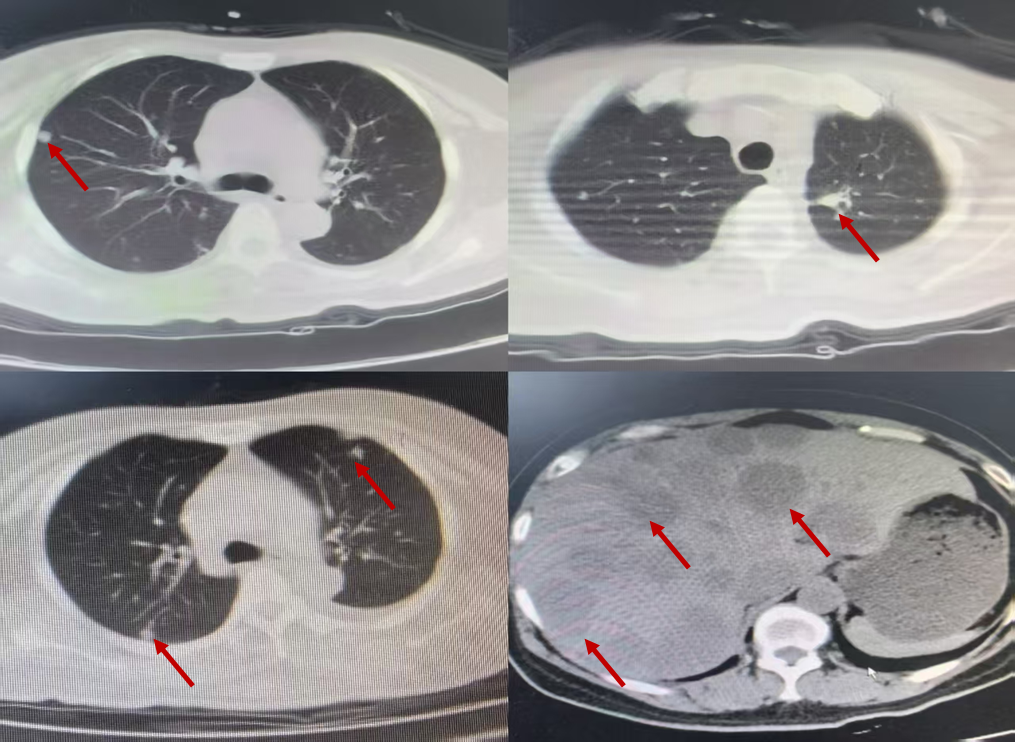

2022-10-12 PET-CT(图1):1.左肺上叶FDG高代谢结节;左肺胸膜多处FDG高代谢灶;双侧锁骨区多发FDG略高代谢小淋巴结、簇状分布;左肺门、纵隔、膈肌脚间隙、上腹部、腹膜后多发FDG高代谢淋巴结;右侧第5前肋、胸骨体、左侧坐骨,肝脏多发FDG高代谢灶,符合肺恶性肿瘤并多发转移。2.左侧胸腔积液。3.右肺上叶磨玻璃结节,未见FDG代谢,肿瘤不除外。

2024年4月29日复查CT(图4):左肺上叶少许条片影、右肺上叶结节均较前相仿;右肺上叶后段磨玻璃密度影较前略增大,双肺另见多个微小结节、类结节,较前略增大;枕骨斜坡、胸腰椎、双侧部分肋骨、双侧肩胛骨、右肱骨头、双侧锁骨及胸骨见多发高密度影,较前范围增大。

2024年4月29日-2024年6月21日,予“洛拉替尼100mg qd”口服治疗。治疗期间,肝功能及血脂异常,出现恶心、呕吐、腹泻不适,无法耐受,减量后仍无法耐受。患者出现腰痛症状,2024-06-21复查胸部+上腹部CT(图5):左肺原发灶增大,双肺新发转移灶,肝内多发转移灶,部分融合成团;查腰椎+骨盆磁共振(图6):骶尾骨、双侧髂骨、坐骨、耻骨及右侧股骨头、股骨颈骨质信号不均,见多发斑片、结节状异常信号影,T1W1、T2W1呈稍低信号,T2W1脂肪抑制序列呈高信号;子宫左侧壁见类圆形异常信号影,边界尚清,大小约5.6cm×5.7cm,T1W1呈等信号,T2W1呈高低混杂信号;所见盆腔内未见明显肿大淋巴结。

2024年6月21日至今,予“长春瑞滨软胶囊40mg/tiw 连服三周休息一周 Q4W+贝伐珠单抗 400mg d1 Q3W+地舒单抗 120mg ih Q4W”联合治疗,同时针对第四腰椎行放疗以止痛。2025-03-26,复查胸部+上腹部CT(图7):左肺原发灶缩小,双肺新发转移灶稍缩小,肝内多发转移灶较前缩小,边界清楚;颅脑磁共振:未见转移。